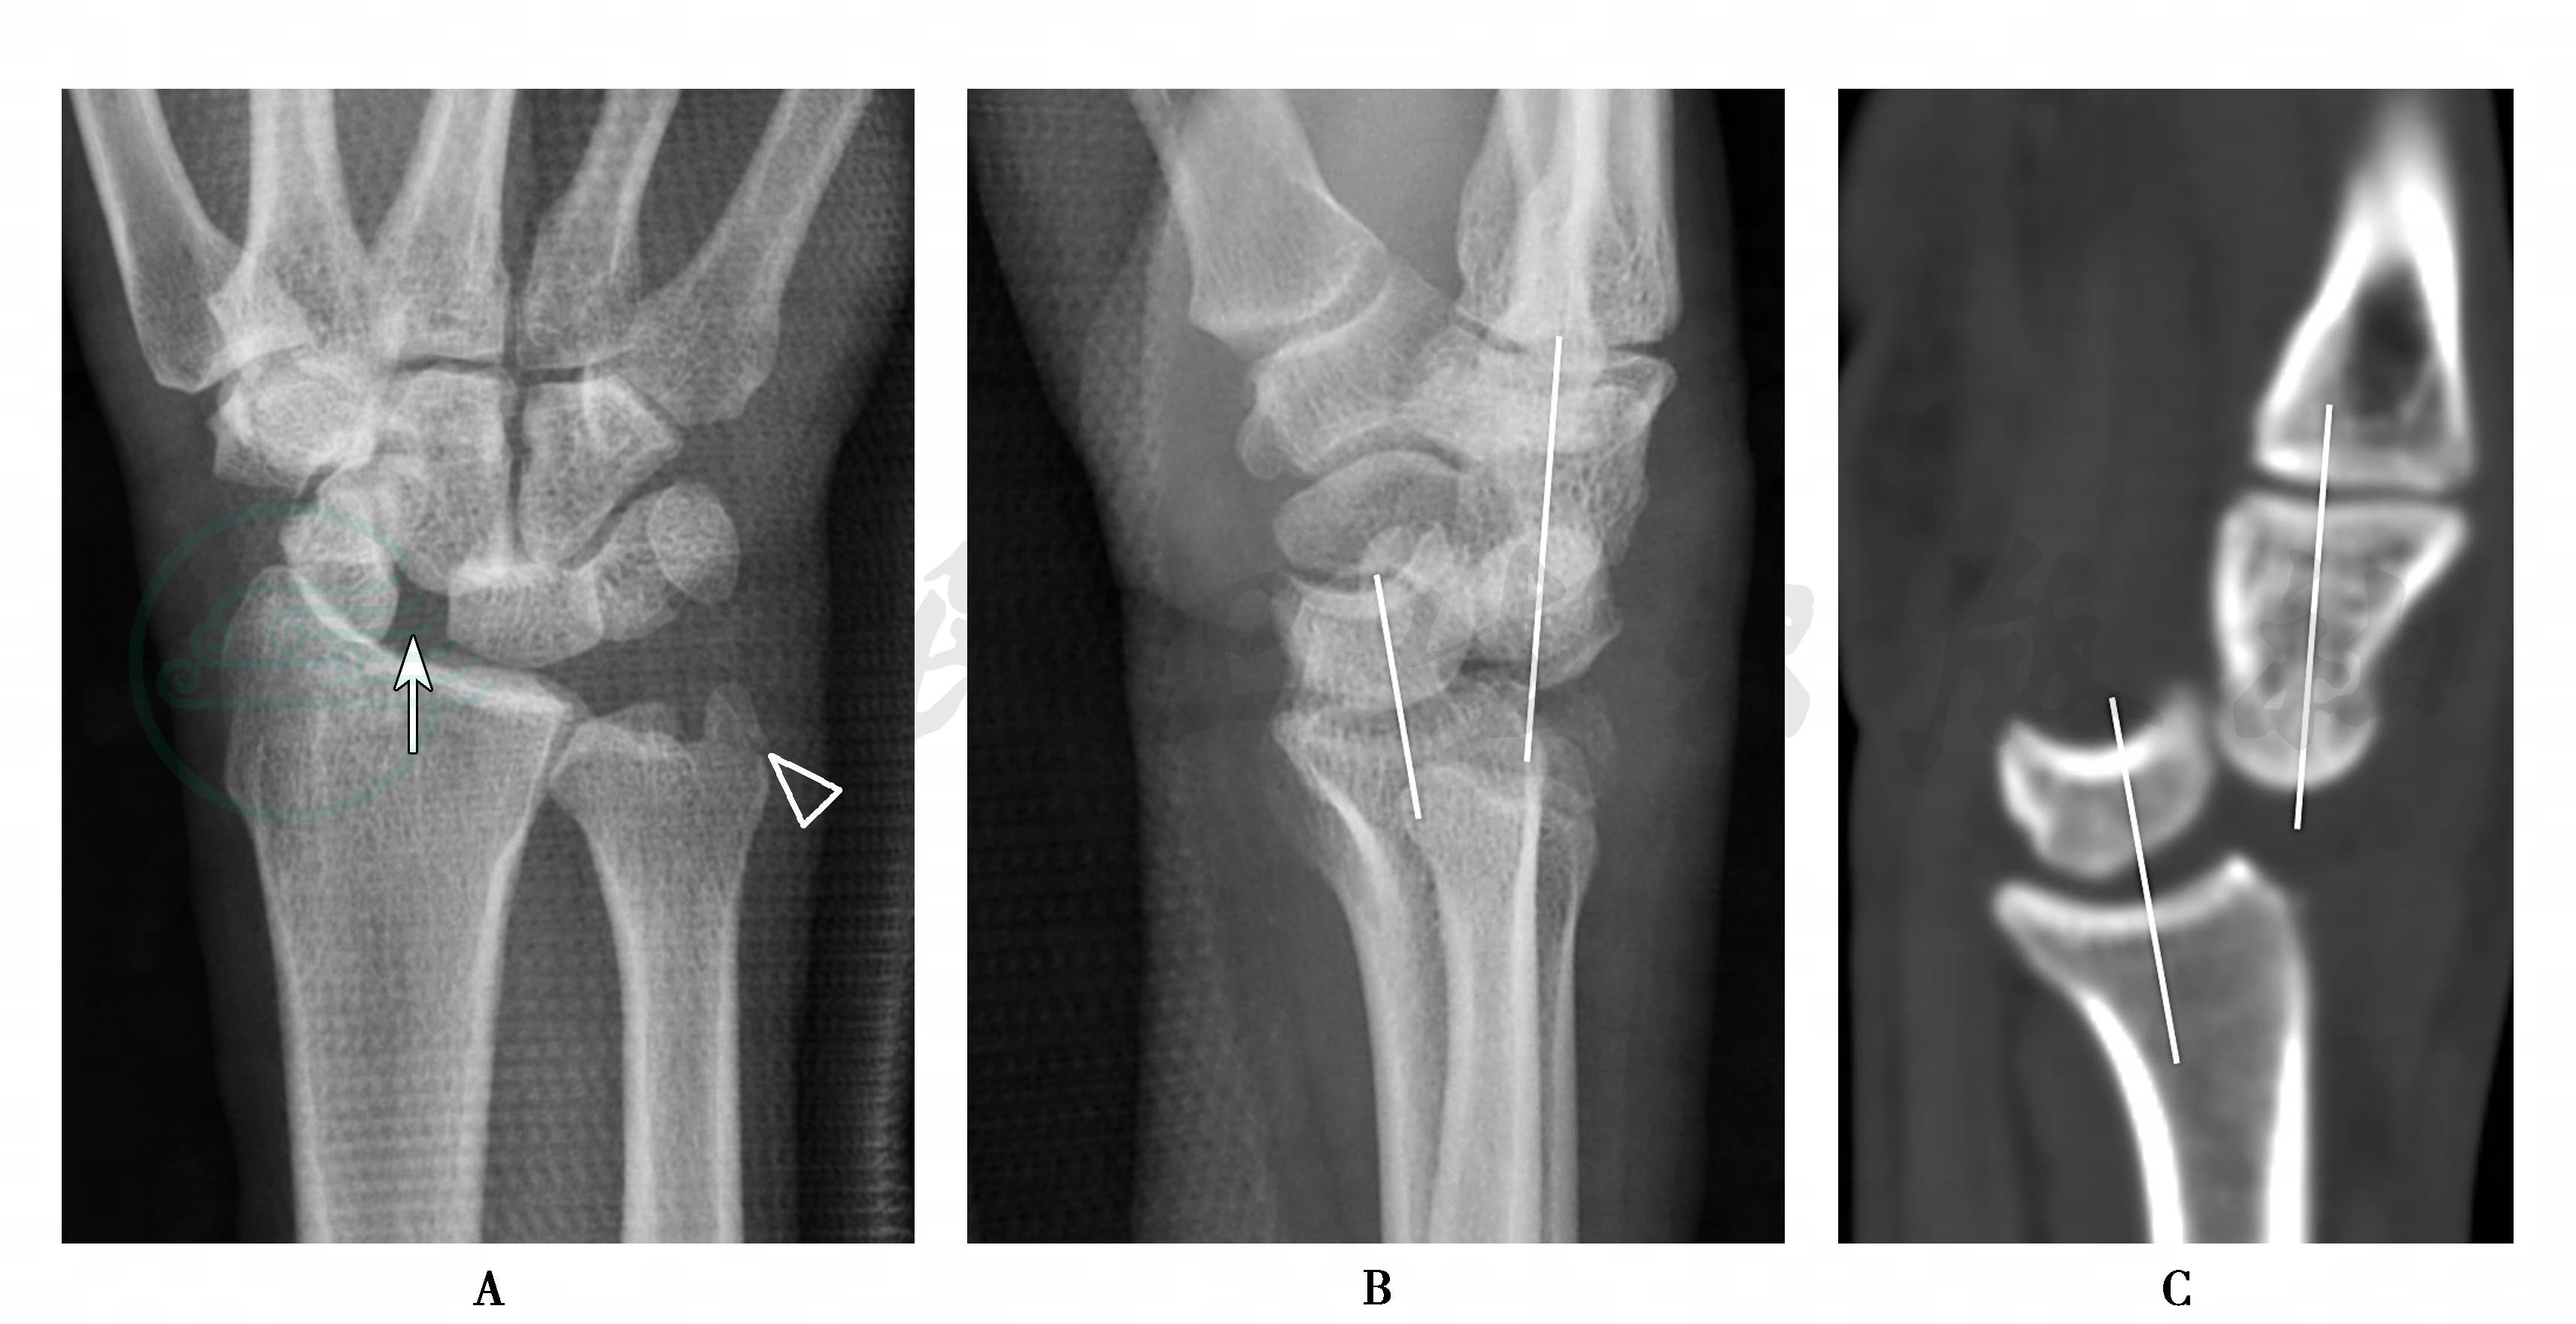

图1月骨周围脱位(背侧)的影像表现

A、B.腕关节后前位及侧位X线片,可见腕关节的外固定影,后前位片显示Gilula线中断,月骨与头状骨、钩骨近端的投影重叠,舟月关节间隙增宽(箭),还可见尺骨茎突骨折(空心箭头),桡骨远端骨质欠规整;侧位片可见月骨与桡骨对位正常,其余腕骨相对月骨向背侧移位。C.矢状位重建的CT图像可以更清晰地显示月骨周围脱位

X线片是主要的检查方法(图1),后前位X线片显示Gilula线中断,腕高减小,近排与远排腕骨重叠,尤其是头状骨与月骨的重叠,腕中关节间隙消失。侧位X线片显示桡骨远端、月骨、头状骨及第3掌骨不再共线,月骨位置正常,其余腕骨通常向背侧或掌侧移位,以背侧移位多见,头状骨近端位于月骨后方。

CT检查对骨骼病变的检测优于X线片,CT冠状面重建图像上可见Gilula线中断,近排腕骨与远排腕骨失去正常对应关系,通常是头状骨向背侧脱位。但桡月关系保持正常;矢状面重建可见桡骨、月骨、头状骨构成的纵轴线在头月关节处发生中断,桡月关节对位正常,月骨远端关节凹空虚,头状骨以向背侧移位多见(图 1C)。